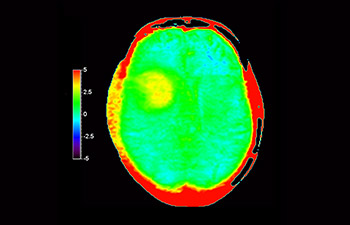

Hirnläsion image

Hirnläsion

mit 3D APT